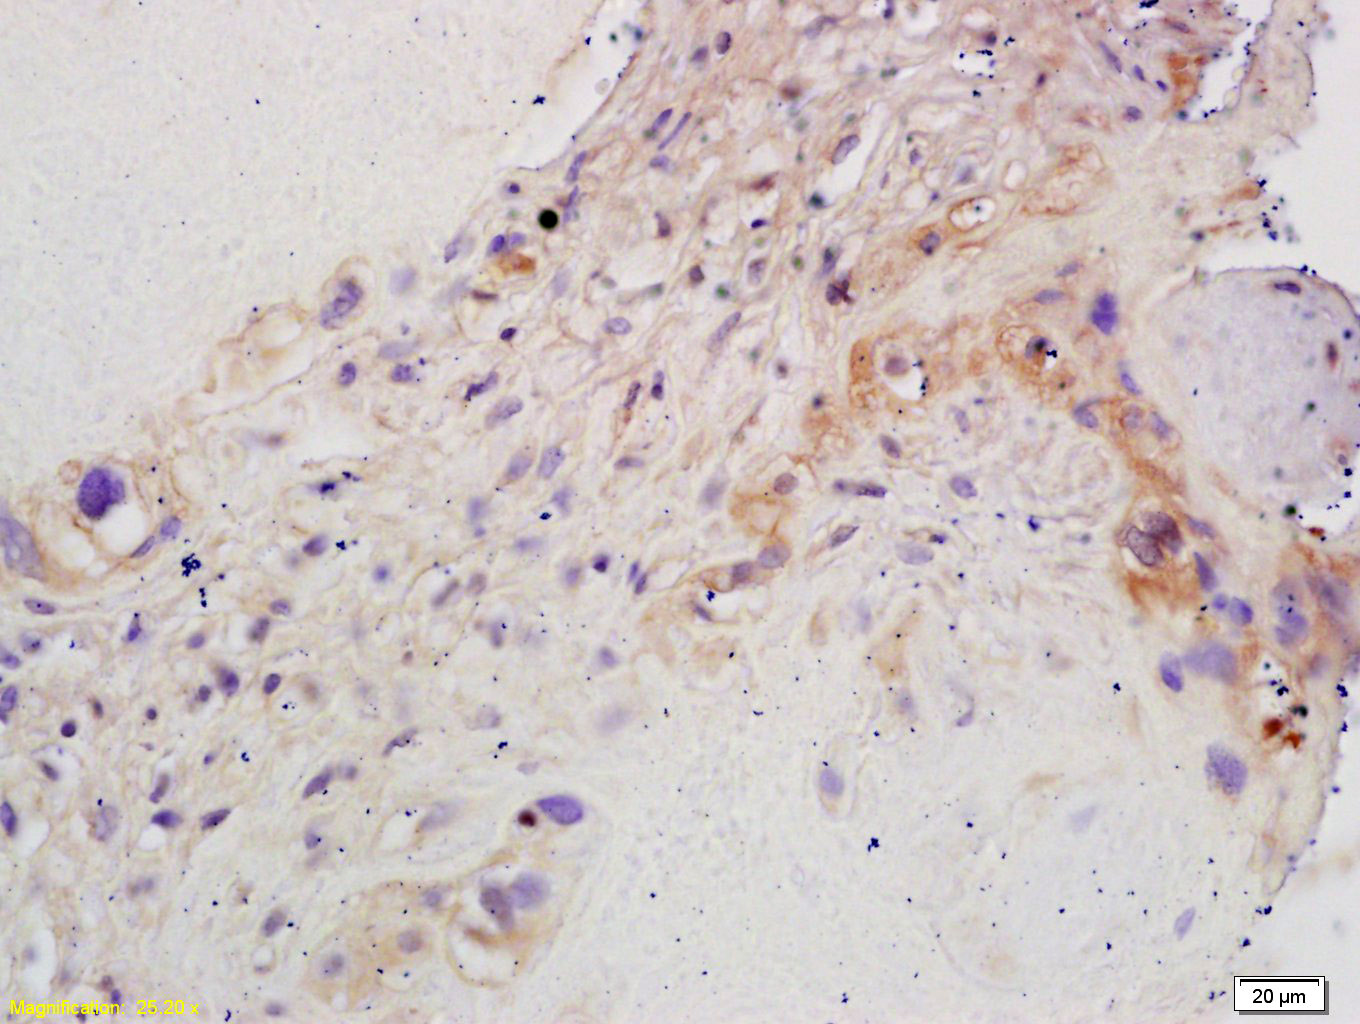

Tissue/cell: human placenta tissue; 4% Paraformaldehyde-fixed and paraffin-embedded; Antigen retrieval: citrate buffer ( 0.01M, pH 6.0 ), Boiling bathing for 15min; Block endogenous peroxidase by 3% Hydrogen peroxide for 30min; Blocking buffer (normal goat serum,C-0005) at 37℃ for 20 min; Incubation: Anti-CYP19/CYP19A1 Polyclonal Antibody, Unconjugated(bs-1292R) 1:200, overnight at 4°C, followed by conjugation to the secondary antibody(SP-0023) and DAB(C-0010) staining